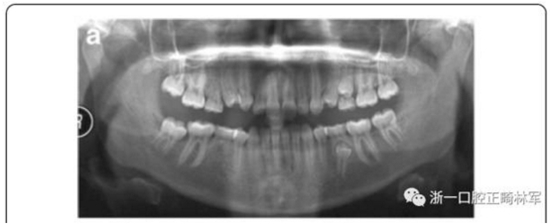

影像學(xué)檢查,右側(cè)第二前磨牙和所有第三磨牙先天性缺失;